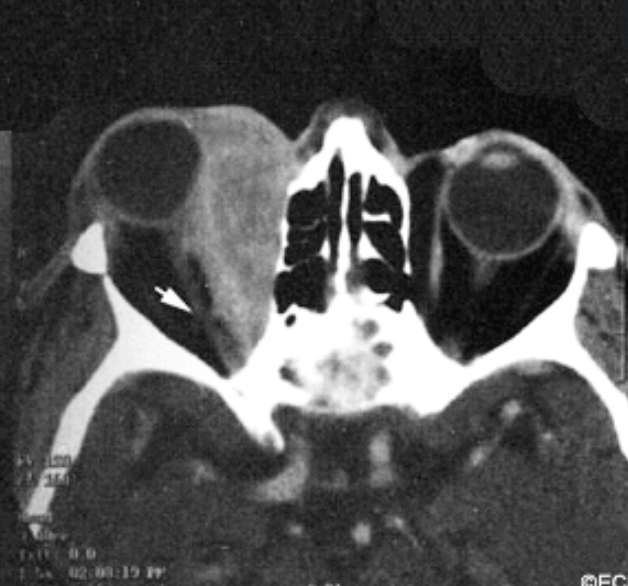

Detection of Occular FB

Wood